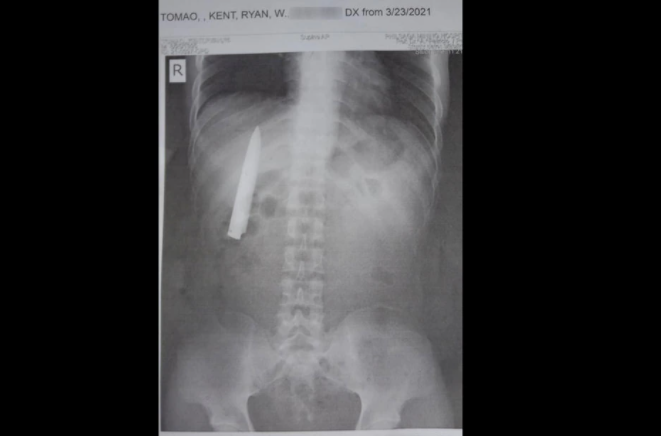

Tờ ABS-CBN ngày 24/3 đưa tin người đàn ông có tên Kent Ryan Tomao, 25 tuổi, phát hiện ra lưỡi dao 10cm găm trong cơ thể khi đi khám sức khoẻ để xin việc vào một công ty khai thác mỏ.

Anh Tomao chụp X-quang và không tưởng tượng được rằng có một lưỡi dao nằm trong ngực mình, chỉ vài cm nữa sẽ đâm vào phổi.

Tại đây, bác sĩ điều trị khâu vết thương và cho Tomao uống thuốc giảm đau, nhưng lại để sót một lưỡi dao gãy nằm sát khung xương sườn của anh.